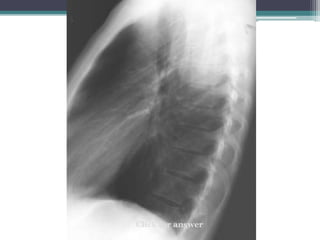

Click for answer

Cervicothoracic sign

โ€ข Answer: Mass is in posterior mediastinum. We

know because it remains sharply outlined in apex of

thorax, indicating that it is surrounded by lung.

โ€ข This particular example is a ganglioneuroma